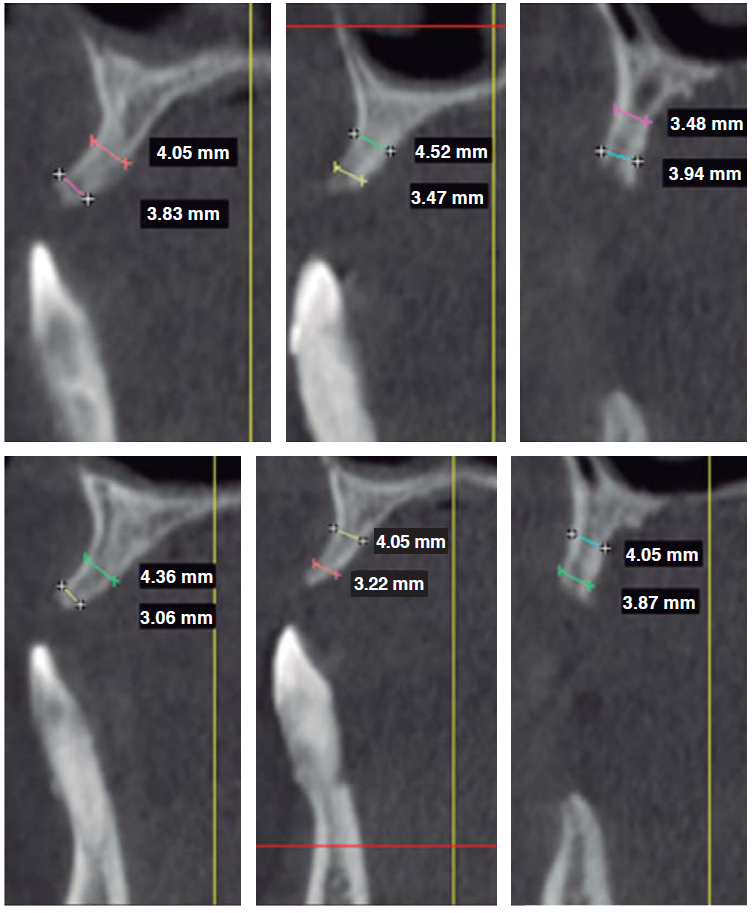

Tomographic evaluation

A cone beam computerized tomography was indicated in order to assess remaining bone availability which could allow implant placement. Tomographic evaluation revealed that, in the upper jaw, in spite of generalized bone resorption, there was sufficient bone mass to place a crown-apical implant. Contrarily, in buccal/palatal direction, no sufficient bone mass was found for conventional implant placement (Figure 2). Therefore, this jaw would correspond to Seibert's class III alveolar ridge deformities, thus, the need arose to perform additional surgical procedures to allow placement of at least six implants.

Figure 2 CBCT showing generalized horizontal bone resorption, although sufficient bone was vertically found in apical-crown direction. From left to right, upper jaw: area of teeth 1.1, 1.2 and 1.4. From left to right in lower jaw: teeth number 2.1, 2.2 and 2.4.

The lower jaw exhibited a bone defect compromising vestibular and lingual aspects of remaining bone at the level of tooth 4.2. Nevertheless, sufficient bone mass was found to place four implants in the inter-foramen area.